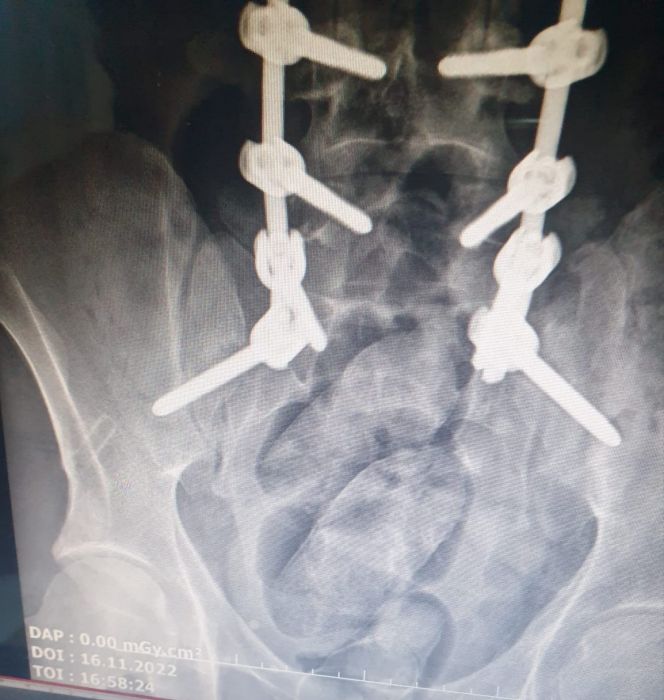

Hasankeyf Mahallesi Çevreyolu Bulvarı'nda gözaltına alınan ve Dr. Yaşar Eryılmaz Devlet Hastanesi'nde muayene edilerek röntgen filmi çekilen şüphelinin midesinde, yabancı cisimler tespit edildi.